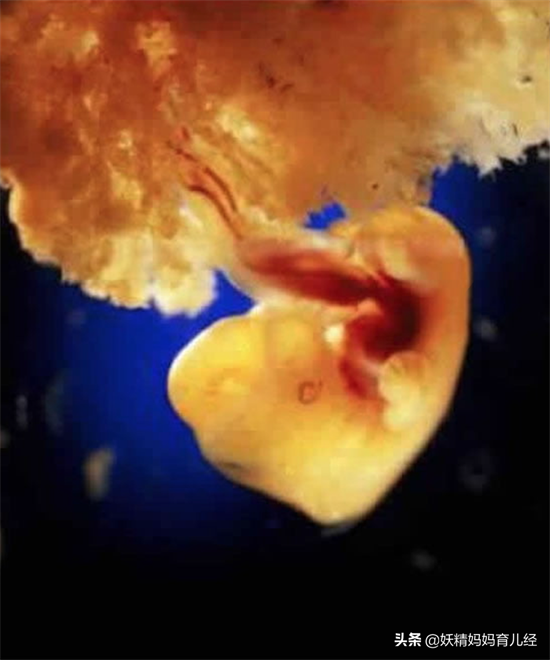

6、受孕后的第八天,他们在子宫壁上安了家。

7、受孕成功后,小家伙最先发育的是脑袋。看上去有点像火星表面。这时候,孕妇该吃啥,自己心里有点数哦。

8、怀孕后的第四周,胎儿还没有发育骨骼,但是你的身体里多了一个人的心跳。咚咚咚。